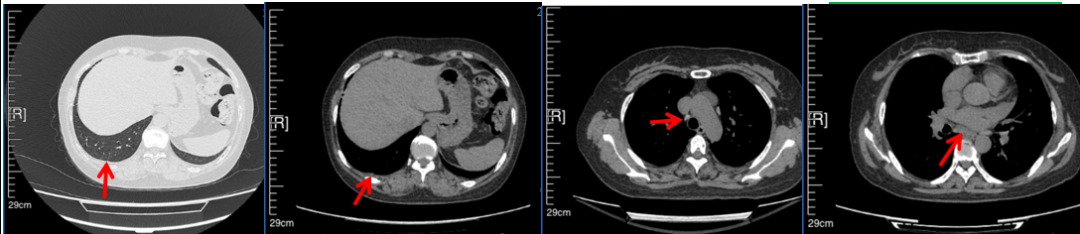

56岁,女性,无吸烟史饮酒史,既往体健。2023年02月患者体检发现肺占位性病变,胸部增强CT:右肺下叶后基底段结节;右侧锁骨上及纵隔内多发淋巴结肿大。PET-CT:右肺下叶周围型肺癌可能性大;1R、2L、3P、4R、4L及7组淋巴结转移可能性大。2023年02月就诊于本院胸外科行超声胃镜下纵隔肿物穿刺活检术,病理:结合免疫组化,符合肺腺癌。行NGS基因检测:EML4:exon20-ALK:exon20融合。PD-L1(克隆号22C3)TPS=55%。

临床诊断:右肺下叶恶性肿瘤cT1bN3M0,IIIB(第9版分期),纵隔淋巴结继发恶性肿瘤,锁骨上淋巴肿继发恶性肿瘤

治疗经过:2023年3月27日始行恩沙替尼靶向治疗至今,最佳疗效为PR,末次评效为维持PR。期间出现轻度肝功能异常(DILI 1级),对症处理后好转。截止目前PFS为26个月。

2023年2月20日基线检查

2024年6月复查PR(最佳疗效)

2024年12月复查维持PR